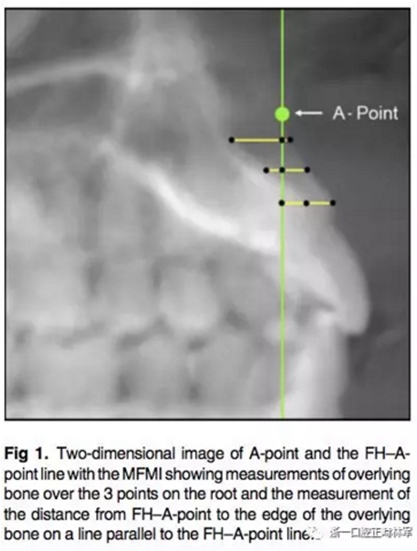

所有圖像導(dǎo)入Dolphin軟件中進行處理,2D側(cè)位圖像為使用Dolphin軟件使用相同的標(biāo)準(zhǔn)切割CBCT獲得。使用眶耳平面(FH)作為水平參考平面,使用垂直于眶耳平面(FH)同時通過A點的直線作為垂直參考平面。在上切牙最前點進行定點,牙根分界為自釉牙骨質(zhì)界至根尖,在牙根根尖、牙長1/2處、釉牙骨質(zhì)界下3mm處進行定點。使用FH的平行線測量頰側(cè)牙槽骨至牙根上3點的距離,同時測量A點與以上三條線段的距離,如圖所示。測量切牙的轉(zhuǎn)矩,使用通過切點、根尖的直線與FH平面的所成角。

在CBCT的3D圖像上使用右側(cè)耳點與眶下點定FH平面。同樣定好過A點與FH垂直的垂直參考線,測量牙根上點至垂直參考線的距離。

根據(jù)每顆切牙相對上頜骨的位置在同一平行切面上各自確定A點,定好切牙最前點(MFMI),牙根長度依然為釉牙骨質(zhì)界至根尖點。使用與2D側(cè)位片上相同的方法進行牙根至骨皮質(zhì)的測量。轉(zhuǎn)矩的測量也同2D側(cè)位片。